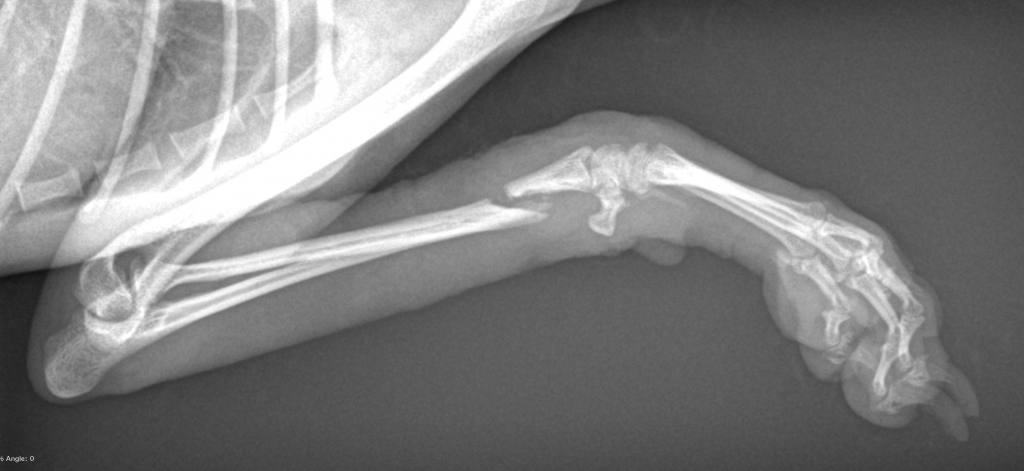

当院にてレントゲン撮影をさせていただいたところ、骨折した箇所は骨が癒合せず溶けて無くなりつつあるという状態でした。

骨折時から3か月も経過して骨がほとんど癒合していないのは何かしら問題が生じている可能性が高いです。

これは「癒合不全」や「癒合遅延」と呼ばれる状況で、折れた骨同士が離れた状態であったり、固定が不十分で骨同士に動揺が見られたり、内部で細菌に感染していることなどが原因で骨同士の融合が起きない骨折の合併症の1つです。